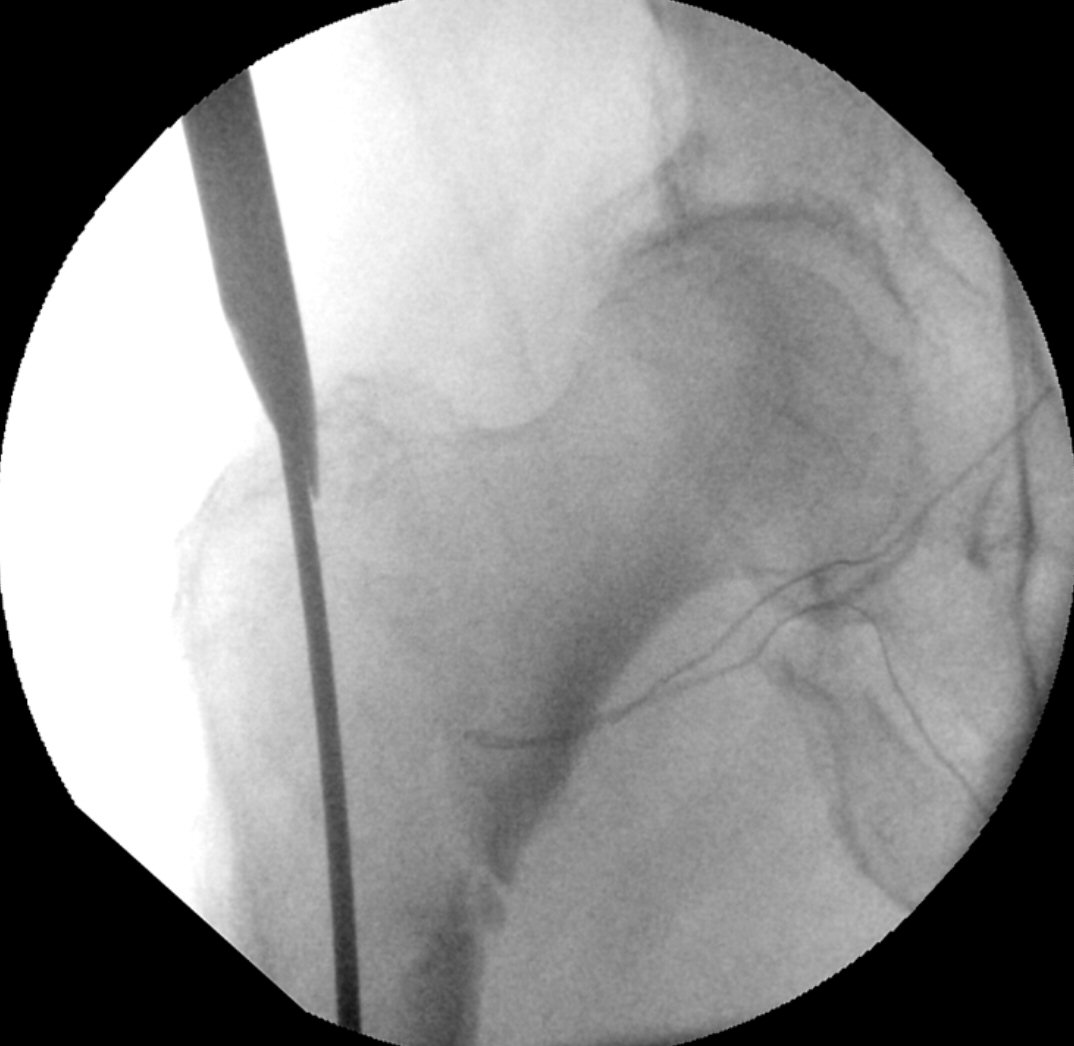

- Borra med k-tråd, följ med genomlysning att tråden har rätt riktning både i frontal- och sidobild, i centrum av kaput på sidobild och strax distalt om centrum av kollum på frontalbild. Borra lagom långt in, änden ska sluta några mm från kaputs kortikala kant.